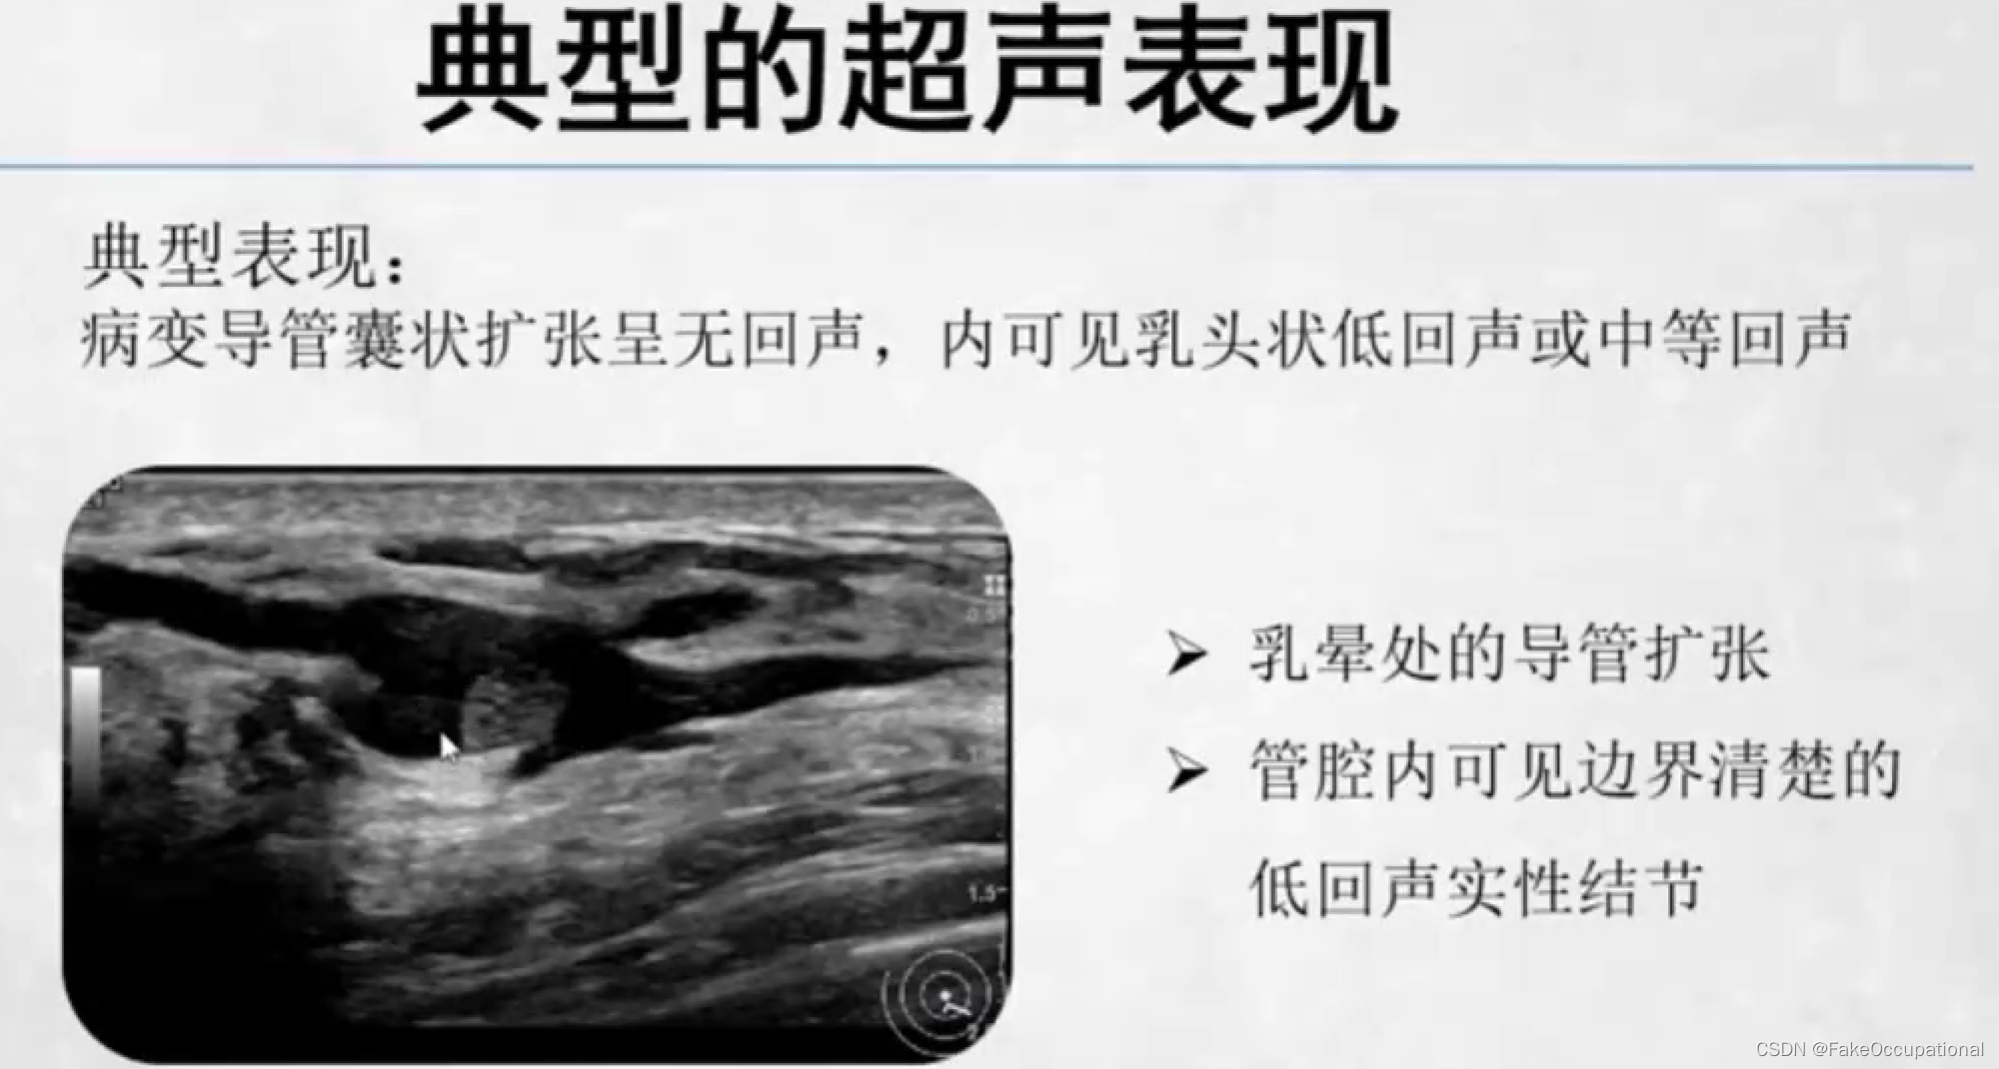

乳腺导管内乳头状瘤